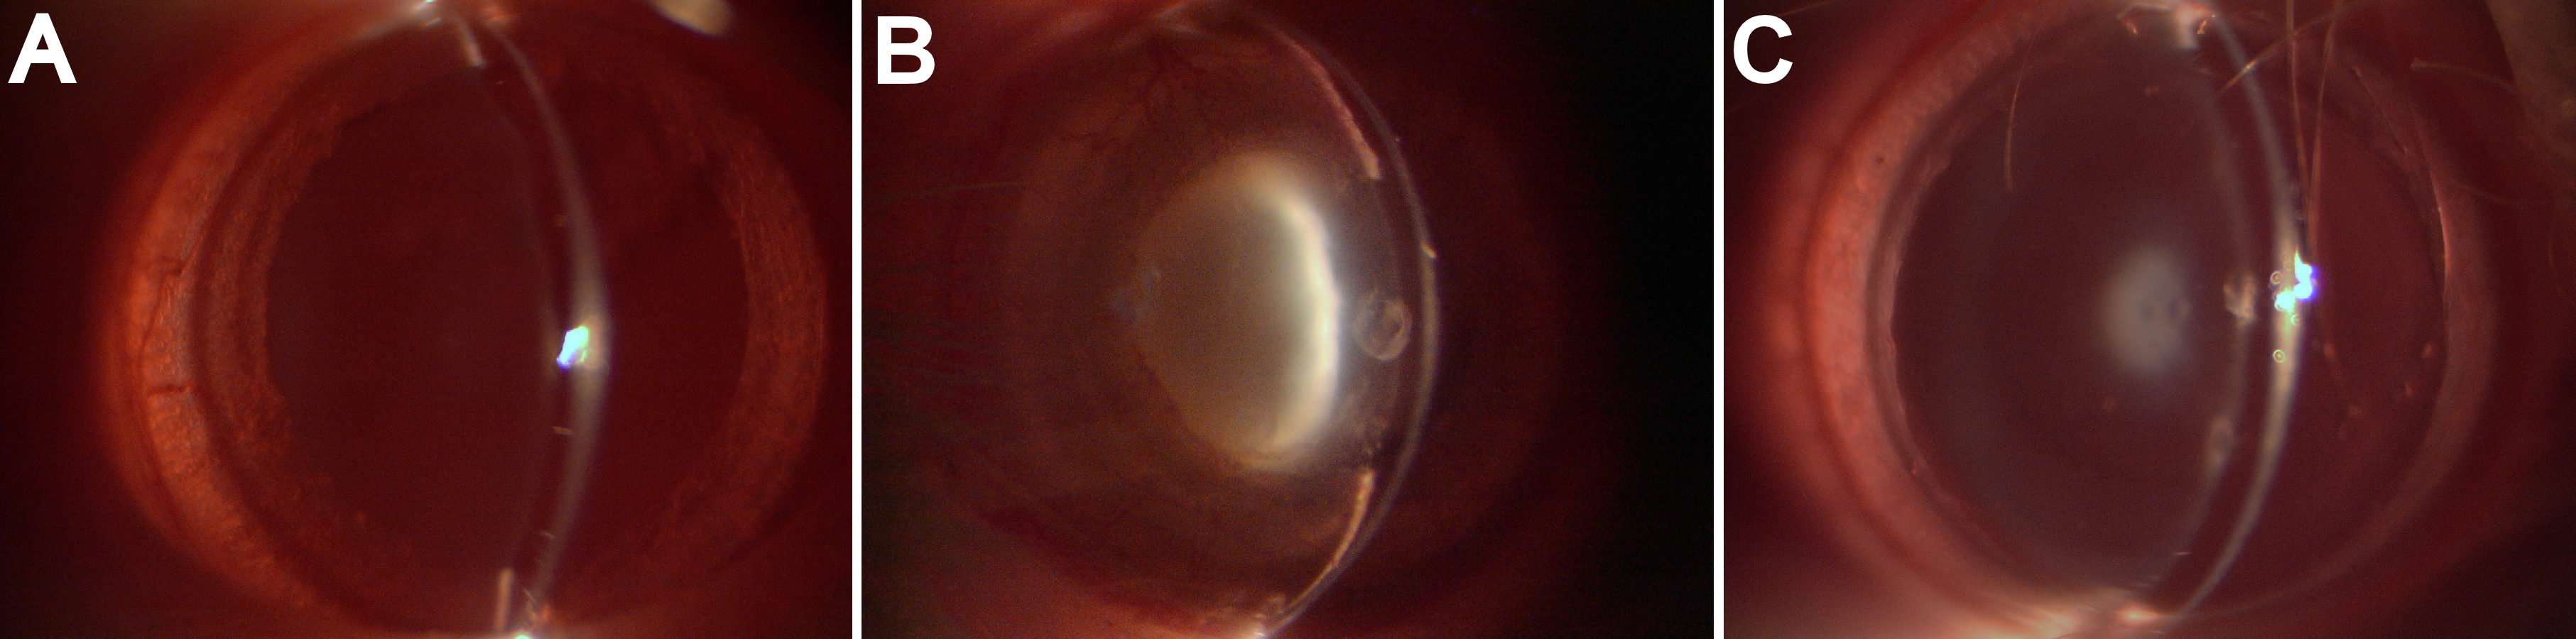

Figure 1. Lens opacification in the eyes of the 26-day-old rat pups under slit-lamp microscope (magnification of 40×) in various experimental

groups. A: Rat pups received only saline (Group A). B: Rat pups received only selenite (Group B). C: Rat pups received selenite and H2 saline (Group C).